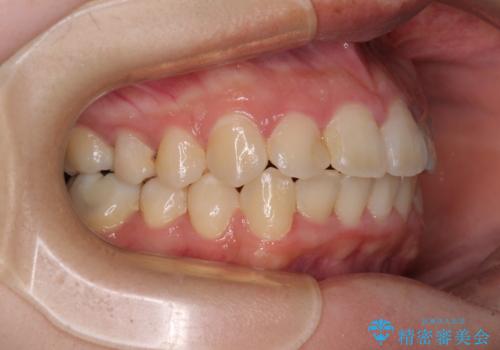

- 上下のデコボコと前歯のクロスバイトを改善したいとのことで来院された患者様です。

極力短期間で治療したいとのことで、ワイヤー装置による矯正治療を行うこととしました。

マウスピースによる矯正治療も提案しましたが、ご自身でのマウスピースの管理の面倒くささと、なるべく早く治療を終えたいとのことで、ワイヤー矯正を選択されました。